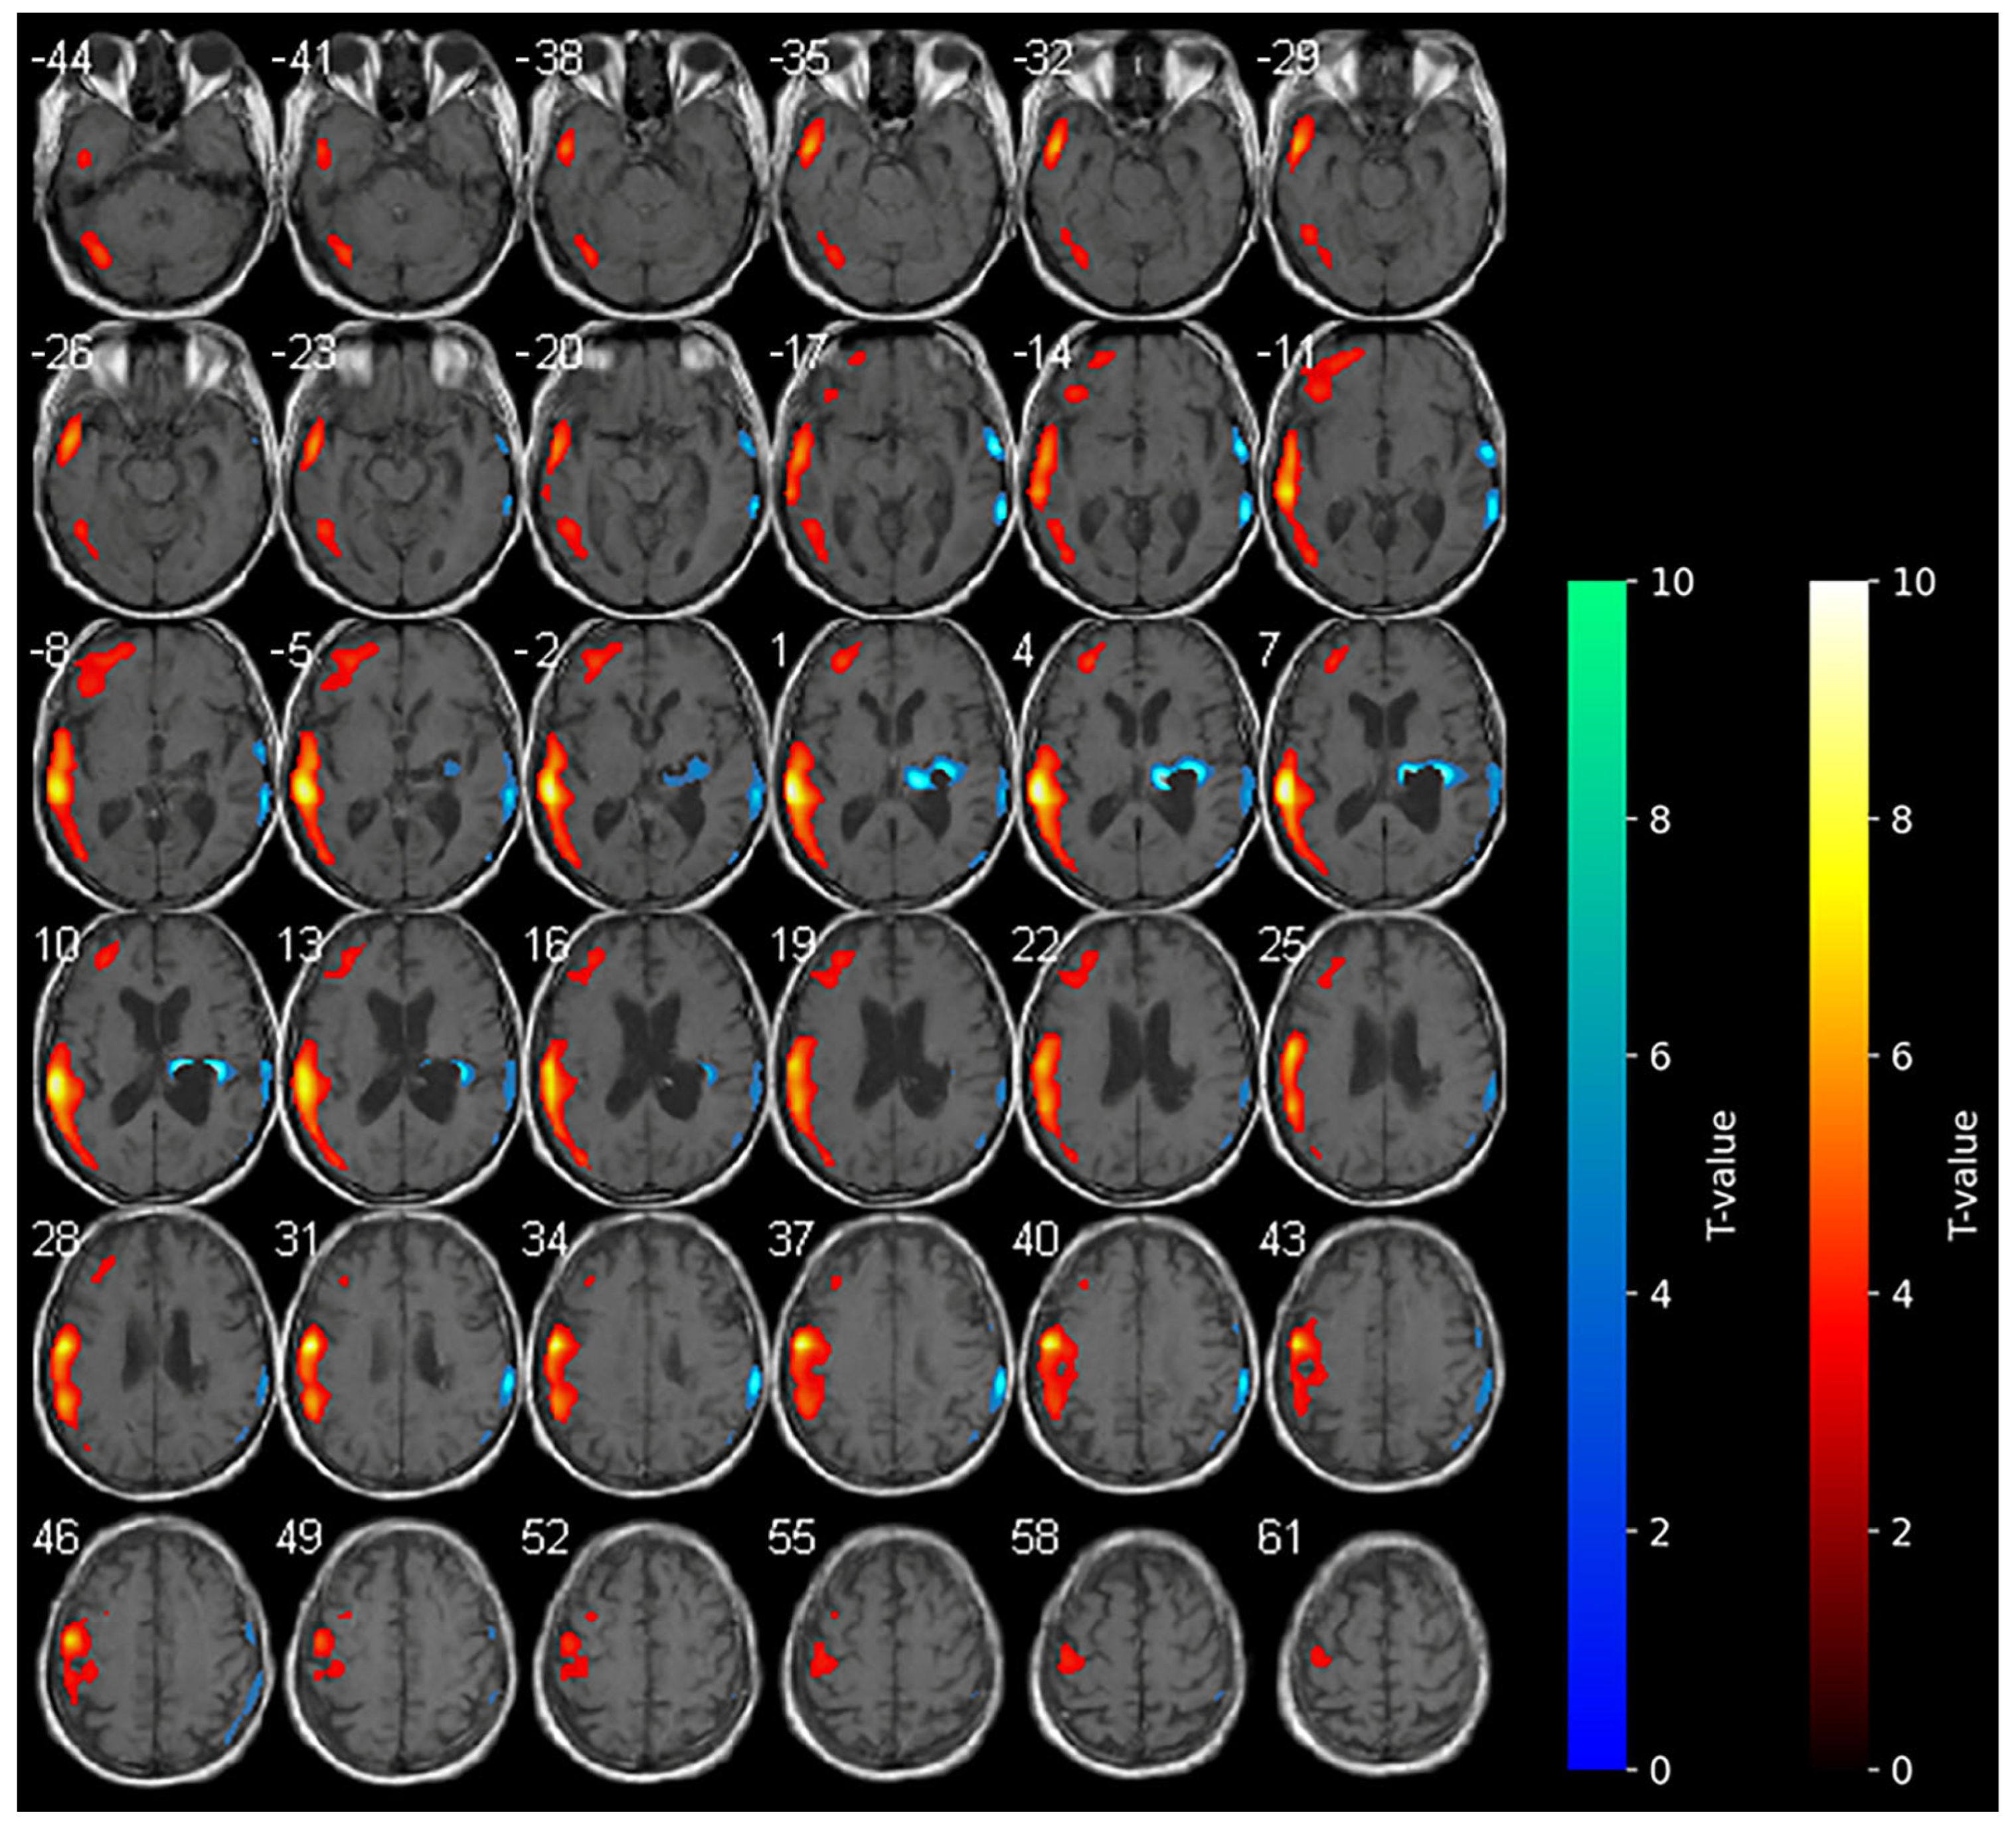

Marked hypometabolism of the right hemorrhagic nucleo-capsular lesion persisted, but interestingly, a reduction in the extension of hypometabolic areas was noted compared with the baseline in the right frontal and parietal cortices. Furthermore, an increase in the uptake of the tracer was detected in the contralateral non-stimulated hemisphere (Figure 2).

During anodal tDCS, consistent with the reported data in the literature, the diffuse areas of hypometabolism observed in the affected hemisphere at the baseline were diffusively reduced, resulting in increased metabolism in these areas. In contrast with the main hypothesis of anodal tDCS functioning, the increase in metabolism in the contralateral unaffected hemisphere during anodal tDCS was unexpected.

The present findings appear to corroborate extant hypotheses concerning the effects of tDCS on patients with stroke [31], but concurrently provide new insights. In our study, we report unexpected brain metabolism in the contralateral hemisphere determined by anodal tDCS. According to the literature, during anodal-tDCS, the widespread areas of hypometabolism observed in the affected hemisphere at the baseline were significantly reduced (see Figure 1), indicating a global increase in the metabolism within the affected hemisphere. The increase in brain metabolism of the contralateral unaffected hemisphere during anodal-tDCS of the affected hemisphere is instead quite unexpected. It is possible that the stimulation of the affected hemisphere conversely modulates anatomical and functional networks activating the contralateral hemisphere [32,33]. The clinical improvements observed in our patient could be related to the reduction in hypometabolic areas in the affected hemisphere following anodal-tDCS, also suggesting the restoration of neuronal activity function in regions previously suppressed due to stroke-related damage. The unexpected increase in metabolism in the contralateral (unaffected) hemisphere may be indicative of a compensatory or network-level reorganization process, in which stimulation of the affected primary motor cortex influences functionally connected regions across hemispheres [11], thereby highlighting the distributed nature of neuroplastic responses to tDCS.

Figure 2. SPM analysis results (t-maps) during anodal-tDCS. The red and blue areas indicate voxels of significantly increased and reduced metabolism in comparison to the normal control subjects, respectively (p > 0.001).